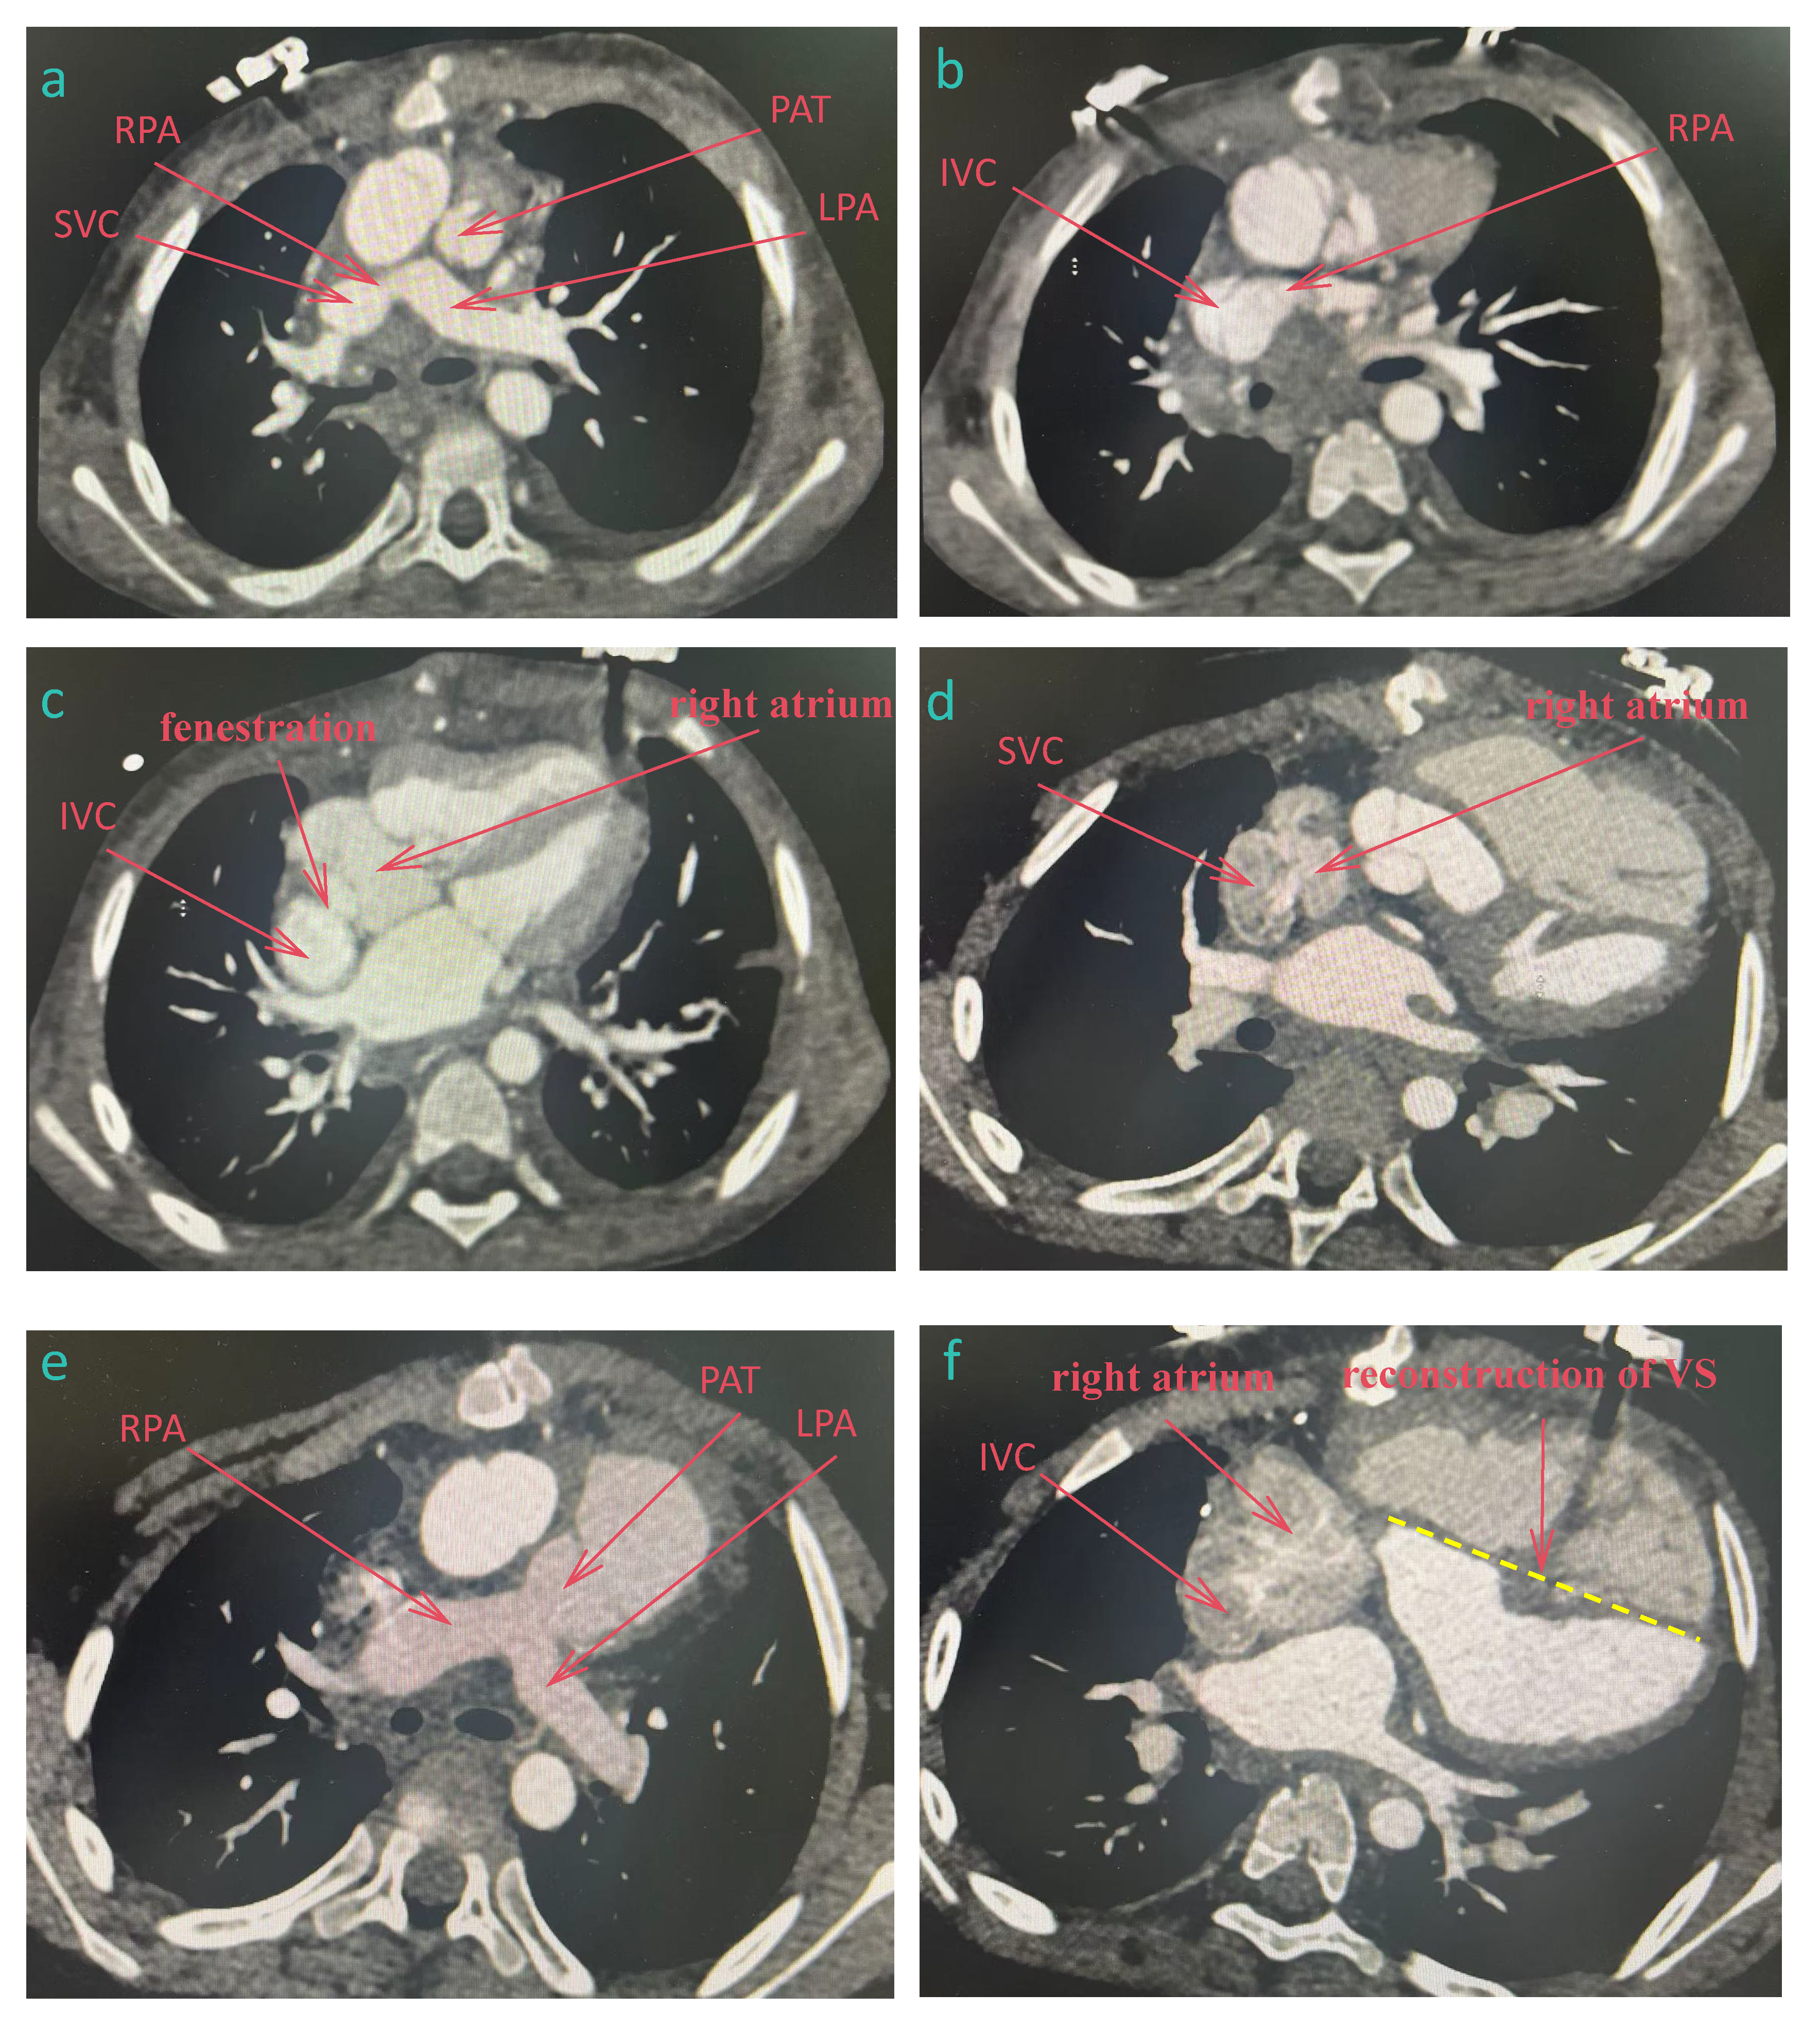

While survival after Fontan surgery has improved substantially, long-term complications remain inevitable. For patients with Fontan failure, heart transplantation is often the ultimate treatment, though the field faces challenges including donor shortages, prolonged waitlists, and elevated post-transplant mortality. A single-center retrospective study by Doulamis et al. demonstrated that BiVC is a safe and effective salvage therapy for Fontan failure, all (n = 23) who underwent elective BiVC survived, whereas 2-year survival rate for patients with a failing Fontan circulation was 72.7% (95% confidence interval, 37%–90%) [53]. Primary BiVC is feasible in patients with mild hypoplastic left heart syndrome, whereas a staged approach with ventricular recruitment is preferred for those with moderate-severe left ventricular dysplasia. Fig. 2 is the computed tomography (CT) data of a patient who underwent TCPC followed by BiVC in our hospital.

Figure 2: CT data of a patient who underwent total cavopulmonary connection followed by Biventricular conversion. (a–c) after TCPC, (d–f) after biventricular conversion. (a): The superior vena cava was connected to the right pulmonary artery, and the pulmonary artery trunk was cut off. (b): The inferior vena cava was connected to the right pulmonary artery. (c): The right atrium was fenestrated and communicated with the inferior vena cava. (d): The superior vena cava was reconnected to the right atrium. (e): Pulmonary artery trunk and pulmonary valve were reconstructed. (f): The inferior vena cava was reconnected to the right atrium and the ventricular septum was reconstructed. SVC, superior vena cava; IVC, inferior vena cava; RPA, right pulmonary artery; LPA, right pulmonary artery; PAT, pulmonary artery trunk; VS, ventricular septum.